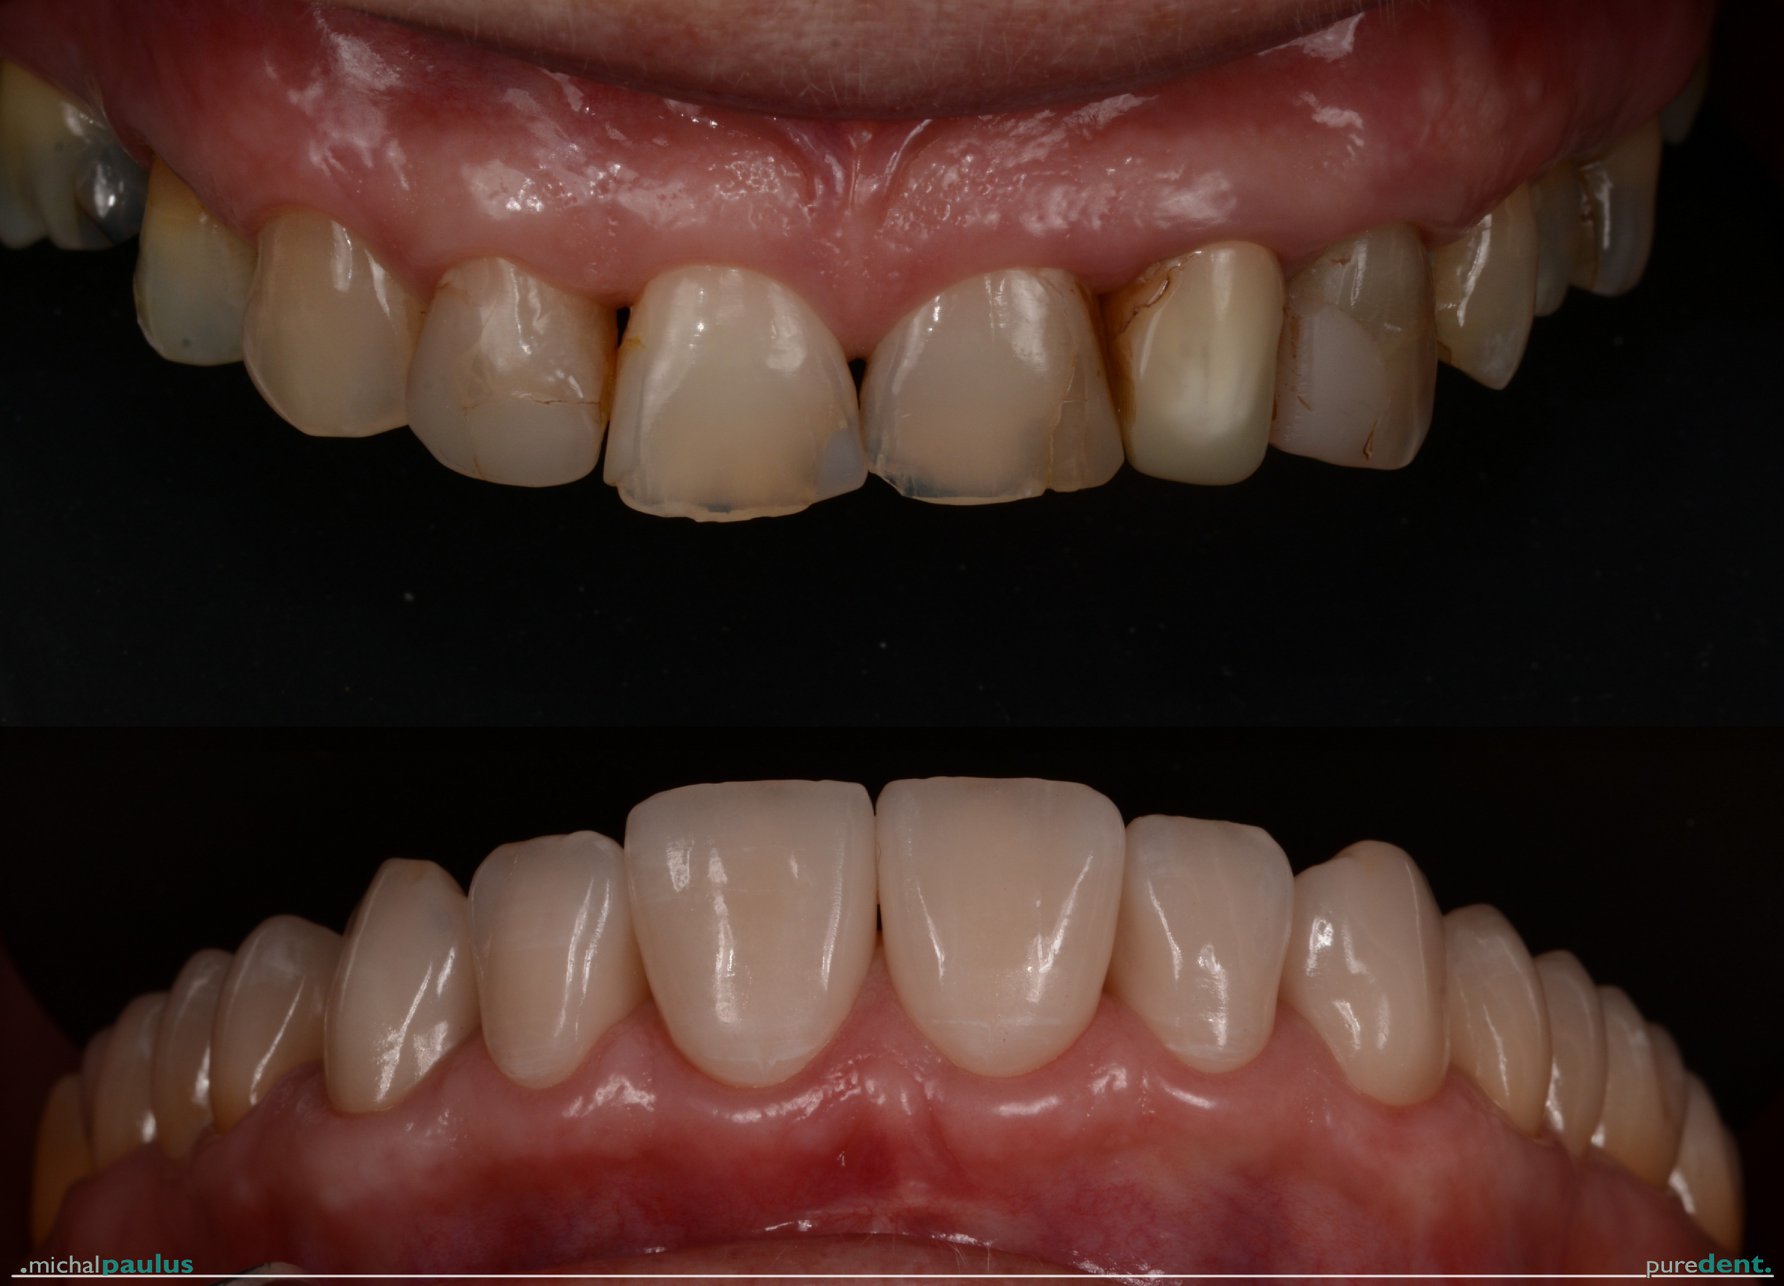

Celková rekonstrukce horní čelisti s ortodontickým předléčením

Celková rekonstrukce horní čelisti s ortodontickým předléčením Celková rekonstrukce horní čelisti s ortodontickým předléčením Celková rekonstrukce horní čelisti s ortodontickým předléčením